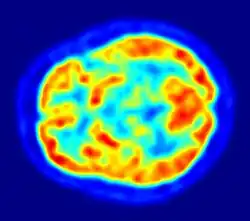

Although the human brain represents only 2% of the body weight, it receives 15% of the cardiac output, 20% of total body oxygen consumption, and 25% of total body glucose utilization.[138] The brain mostly uses glucose for energy, and deprivation of glucose, as can happen in hypoglycemia, can result in loss of consciousness.[139] The energy consumption of the brain does not vary greatly over time, but active regions of the cortex consume somewhat more energy than inactive regions, which forms the basis for the functional neuroimaging methods of PET and fMRI.[140] These techniques provide a three-dimensional image of metabolic activity.[141] A preliminary study showed that brain metabolic requirements in humans peak at about five years old.[142]

Functional neuroimaging techniques show changes in brain activity that relate to the function of specific brain areas. One technique is functional magnetic resonance imaging (fMRI) which has the advantages over earlier methods of SPECT and PET of not needing the use of radioactive materials and of offering a higher resolution.[157] Another technique is functional near-infrared spectroscopy. These methods rely on the haemodynamic response that shows changes in brain activity in relation to changes in blood flow, useful in mapping functions to brain areas.[158] Resting state fMRI looks at the interaction of brain regions whilst the brain is not performing a specific task.[159] This is also used to show the default mode network.